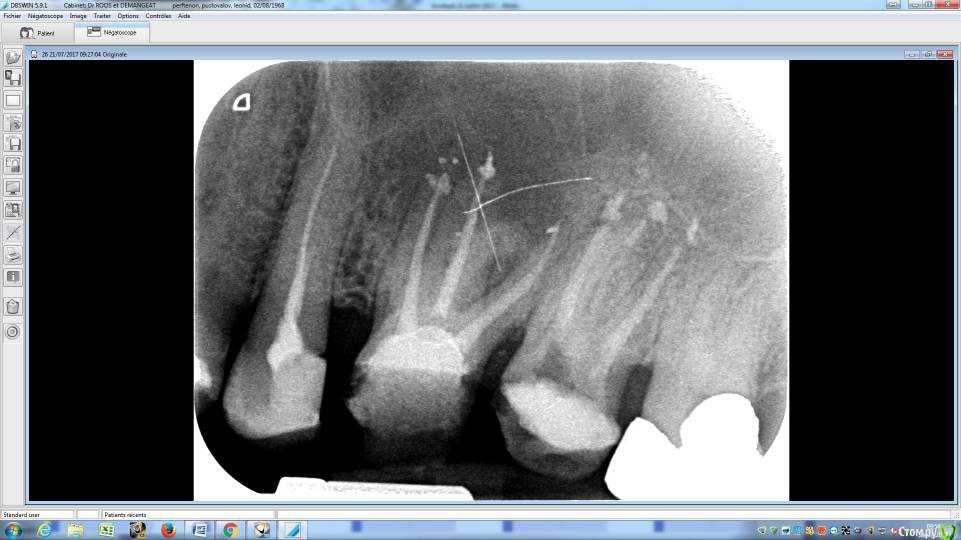

LeoRuss Опубликовано 20 февраля, 2018 Поделиться Опубликовано 20 февраля, 2018 (изменено) Здравствуйте уважаемые метры, в очередной раз обращаюсь к вам за советом.Чуть меньше года назад эндодонтическим методом в полном соответствии с вашими рекомендациями была пролечена киста 26.( http://forum.stom.ru/topic/34508-podsadka-kosti-pri-kiste-nuzhna-li-v-dannom-slucha/ ) При вскрытии зуба выявилась неприятная картина: оба титановых штифта в далеком ‘94м были завернуты мимо корневых каналов прямо в челюсть ;(Док все демонтировал, прочистил под микроскопом и каналы и дыры от штифтов и замуровал МТА : спустя 8 месяцев - 10/2017 : И вроде бы все чудесно, но пару раз за это время десна вокруг зуба воспалялась, и зуб становился более подвижным, но все проходило после 2-3-5 дневного интенсивного полоскания хлоргексидином. Три недели назад была наконец то установлена коронка на соседний 27й, десна с внутренней стороны 26ки тогда была тоже припухшей и протезист посоветовал сходить на контроль к эндодонтисту. Напросился и сходил через неделю, десна за это время еще чуть распухла (только со стороны языка), стало больно при легком нажатии на десну в районе верхушки корня ближнего к 25ке и при покачивании зуба. Док сделал снимок, сказал что все чисто и он понятия не имеет почему все надулось. Вариант удаления забраковал, сказал что по его мнению все хорошо, и можно уже ставить коронку. А вот в импланте смысла никакого, тем более что кости для него пока недостаточно, тк межкорневая область еще не дозаросла. Посоветовал терпеть и.. поставить коронку, тк нагрузка на зуб при жевании должна активировать заживление.Но жевать на этой стороне я стал почти месяц назад, сразу после установки временной коронки на 27, вот с тех пор с 26кой все хуже и хуже. За последние полнедели опухоль сильно увеличилась, и между 25/26, и в сторону нёба, дергает в ритме пульса. Появились отголоски боли в носоглотке и в заглазье.Терпеть уже плохо получается, да и смысла не вижу. Вижу два варианта:1. Удалять 26 чтоб не мучаться, с последующей имплантацией, но как быть с нехваткой кости?2. Вскрыть каналы и прочистить еще раз, но даст ли это хоть что то, да и возможно ли в принципе? В любом случае хотел бы узнать ваше мнение, спасибо ! Изменено 20 февраля, 2018 пользователем LeoRuss Ссылка на комментарий

LeoRuss Опубликовано 20 февраля, 2018 Автор Поделиться Опубликовано 20 февраля, 2018 Как вы и говорили сделали томограмму и все прояснилось: киста зажила наполовину но.. по вертикали, та часть кисты что со стороны щеки затянулась, а вот со стороны языка, только чуть. Видимо повлияла перфорация челюсти штифтом, или МТА туда просто не попало. Увы, теперь уже только удаление. Еще раз огромное спасибо ! Ссылка на комментарий